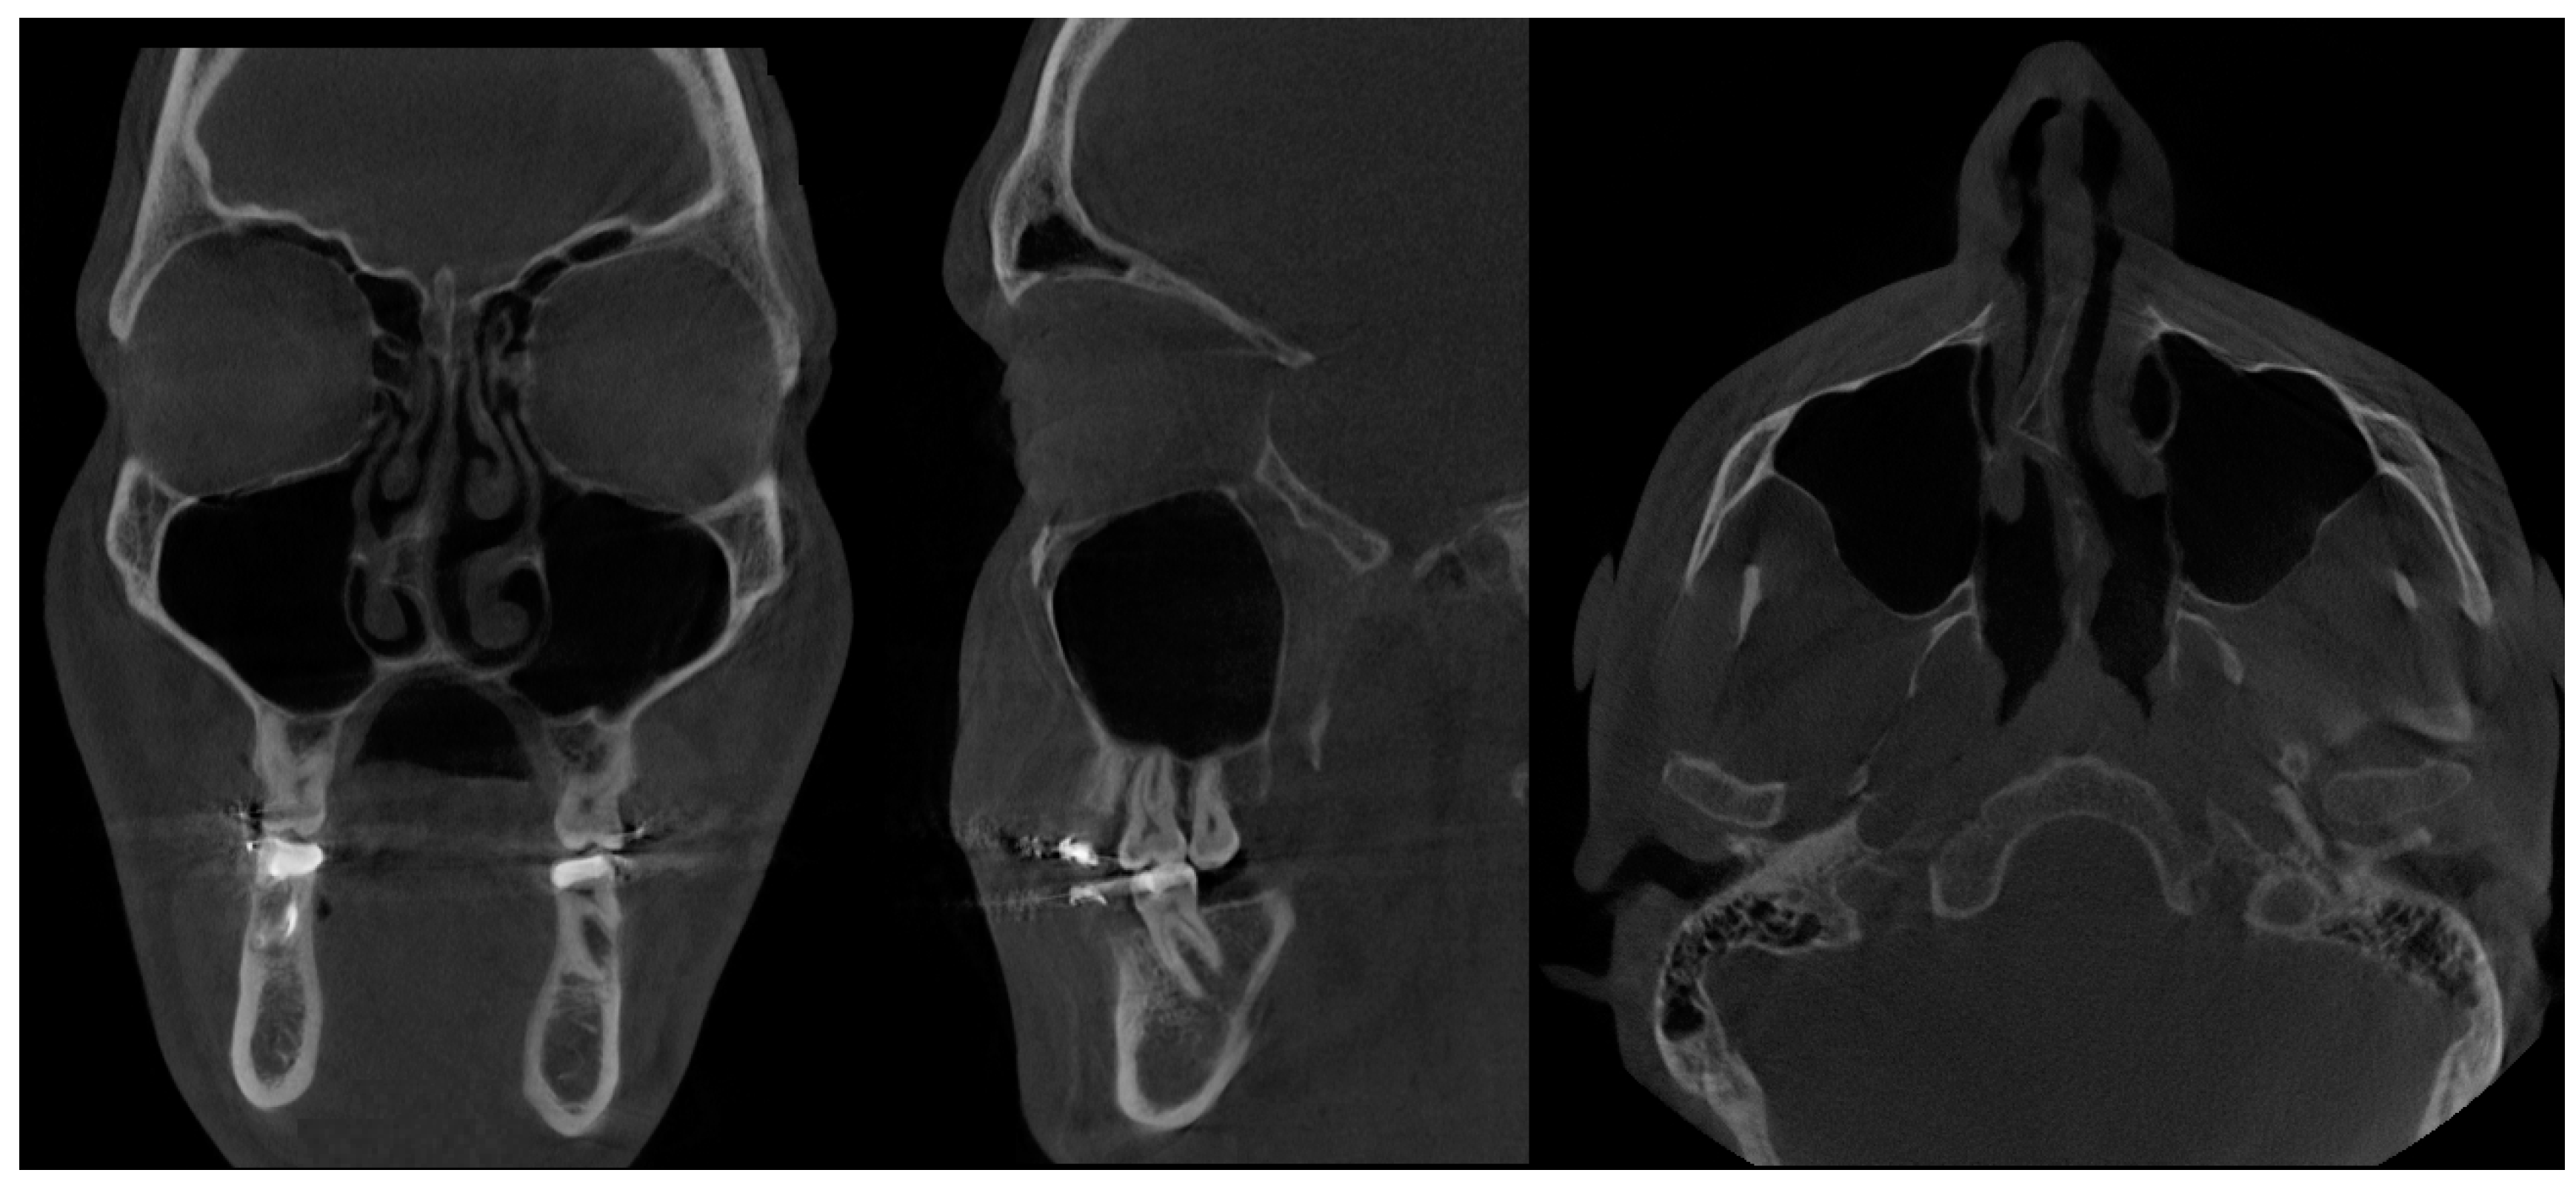

- Type 1 SSS (pure SSS = pSSS) (Figure 2) MS four (4) wall retraction, OMC not patent, opacification present;